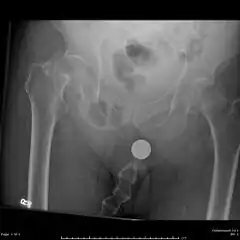

Bilateral femoral neck fractures

Anterior-posterior (AP) and lateral radiographs are typically obtained.[4]

In order to rule out other injuries, hip, pelvis, and knee radiographs are also obtained.[5]

The hip radiograph is of particular importance, because femoral neck fractures can lead to osteonecrosis of the femoral head.[4]